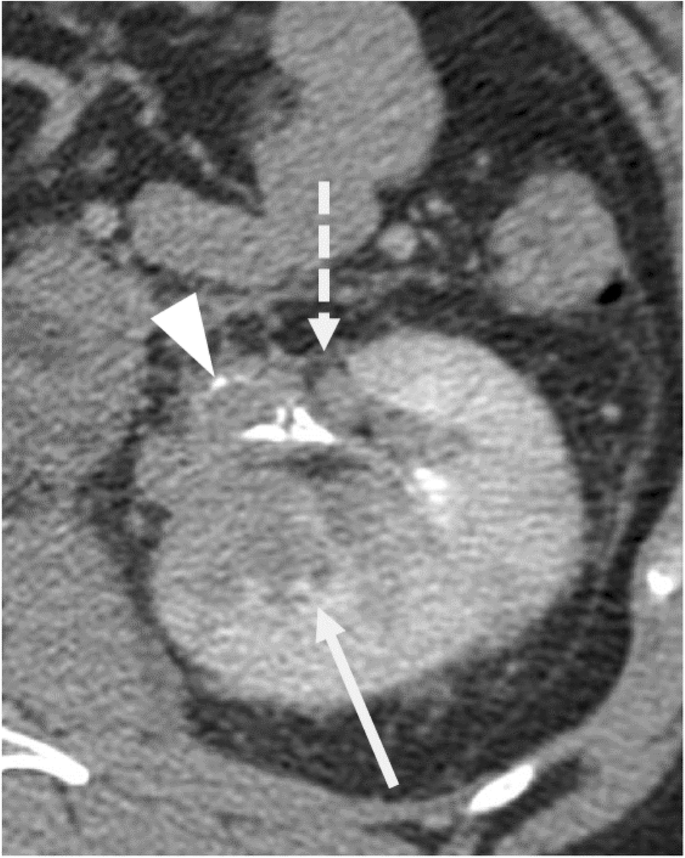

Imaging findings are summarized in Table 2. Tumors ranged in size from 2.2 cm to 18 cm (mean 10.3 cm, median 9.8 cm) and had an infiltrative rather than circumscribed margin in the majority of cases (14/16, 88 %) (Fig. 1). Regarding general tumor features, a large cystic tumor component involving greater than 75 % of the tumor was seen in 8/16 (50 %) of tumors (Fig. 2). Tumor invading the renal sinus fat was seen in 13/16 (81 %) of tumors, hilar collecting system invasion in 8/16 (50 %) (Fig. 1), and renal vein tumor thrombus in 6/16 (38 %).

Regarding modality-specific features, all patients had heterogenous tumor enhancement on MRI and CT, and heterogenous T2 signal on MRI (Fig. 3). Of those patients who had diffusion-weighted imaging available for review (n = 11), all had diffusion restriction in the solid portions of the tumor. On MRI, T1 hyperintense hemorrhage was present in 7/12 (58 %) of cases (Fig. 4). No tumors had intravoxel fat on MRI. On CT, no tumors had calcifications. Of the three patients who had an FDG PET/CT, all had high metabolic activity (mean SUVmax 16.4, range 9.6–21.9), as shown in Fig. 5. An example of the gross and histologic features of one of the renal tumors is shown in Fig. 6.